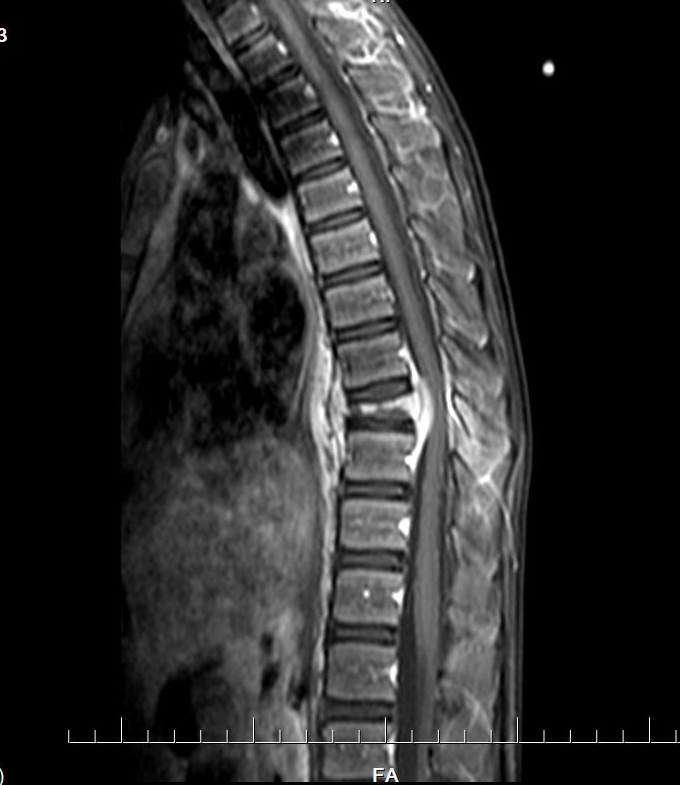

入院CT:结合MRI考虑,T9椎体病理性压缩性骨折,双侧椎弓根骨折,伴周围软组织感染性改变。

胸椎MRI平扫+增强扫描:第9胸椎椎体及其周围软组织感染性病变,并第9胸椎椎体病理性骨折。以结核性感染可能性大。

CT

椎体脊柱病变可单发或多发,椎体可呈楔形或完全变扁呈钱币状,亦可呈溶骨性破坏,很少累及相邻的椎体椎间隙。CT及MRI可多层面显示椎体及附件的溶骨性破坏椎体的溶骨性破坏。常累及一侧椎弓根,同时还可清楚显示椎旁的软组织肿胀和包块,亦可显示椎管内受累的情况。